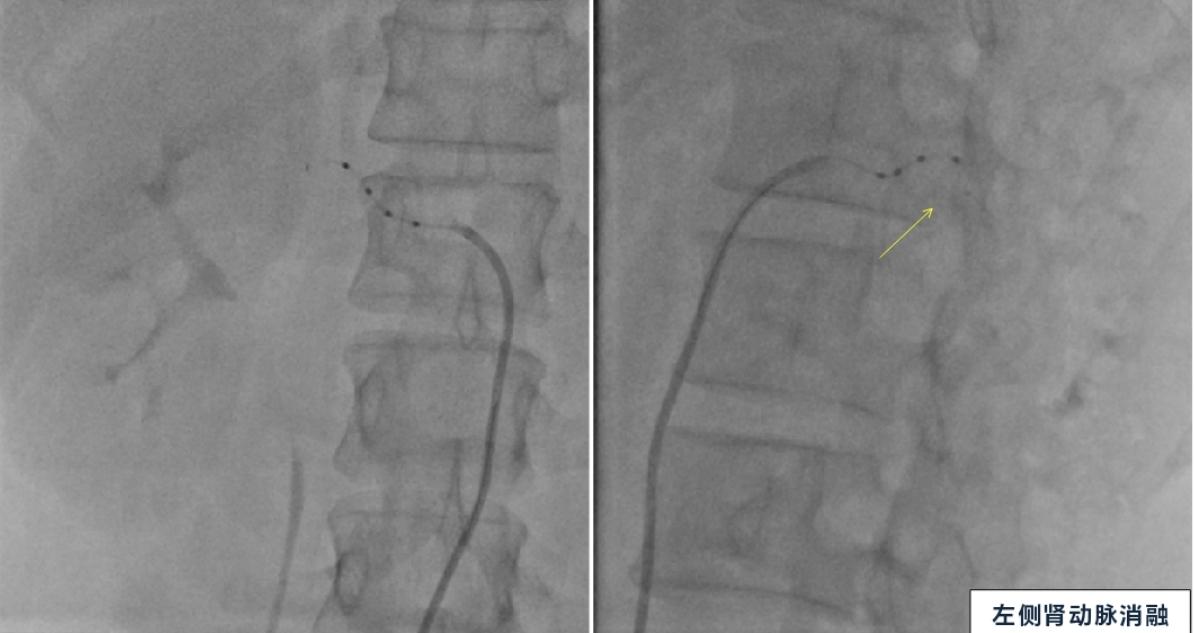

夏文豪团队对孔女士双侧肾动脉主干及分支进行了全面、精准的消融,共消融38个靶点,手术仅仅用了1小时。“在药物镇静后,我们会在患者的大腿根部股动脉穿刺置管,消融导管通过股动脉最后到达肾脏动脉。导管电极贴靠着血管壁,即可完成消融,最后移除导管,患者体内无任何植入物留存。在这个过程中血管壁不会受到损伤,但附着在肾动脉周围的神经被破坏后,活性减弱进而实现降压的目的。” 夏文豪教授介绍手术过程。